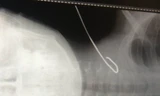

Trước đó, vào khoảng 21h30 ngày 8/10, anh Chung nhập viện trong tình trạng lơ mơ,choáng, mạch và huyết áp không đo được, ngực trái vết thương dài 2cm. Sau khithăm khám, các bác sỹ xác định anh Chung bị thủng tim, chỉ định phẫu thuật khẩnbằng phương pháp mở ngực để khâu vết thương tim.

Song, sau khi mổ, thể trạnganh Chung rất yếu, phải thở máy… Tiến hành kiểm tra, các bác sỹ phát hiện anh Chungcòn bị thủng gốc động mạch chủ bên trong tim, tạo luồng thông từ gốc động mạchchủ vào thất phải. Trước tình huống này, các bác sỹ Bệnh viện Đa khoa tỉnh Khánh Hòa đã hội chẩn với các bác sỹ Bệnh viện ChợRẫy (TPHCM) để tìm phương án cứu bệnh nhân.

Theo bác sỹHùng, đây là trường hợp rất hiếm gặp, nguyhiểm vì bệnh nhân vừa bị thủng thànhtim bên ngoài vừa bị thủng gốc động mạch chủ bên trong tim. Khi bệnh nhân vàocấp cứu, các bác sỹ chỉ phát hiện vết thương tim thì chỉ xử lý, khâuthành tim bên ngoài. Thời điểm đó, chưa thểđánh giá có vết thủng bên trong hay không. Muốn xác định có tổn thươngbên trong thì sau khi đóng vỏ bên ngoài mới kiểm tra được luồng thông bên trong.“Nếu không được phát hiện, phẫu thuật kịp thời thì gần như bệnh nhân sẽ tử vongvì suy tim cấp”, bác sỹ Hùng nói.